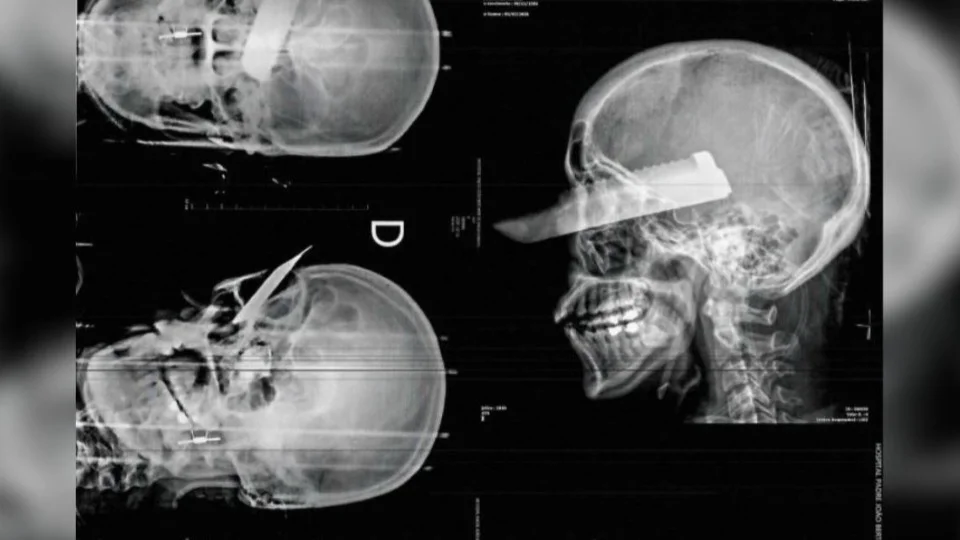

A vítima contou que foi espancada com socos, chutes e golpes com o próprio celular, além de ter sido ameaçada de morte. Em determinado momento, o homem saiu de casa com uma enxada. Ao tentar fugir, ela foi alcançada e atingida com uma facada no rosto, que ficou cravada na cabeça.

O médico que realizou o atendimento confirmou múltiplos hematomas na face, braço e perna esquerda, além de uma lesão grave em um dos olhos.